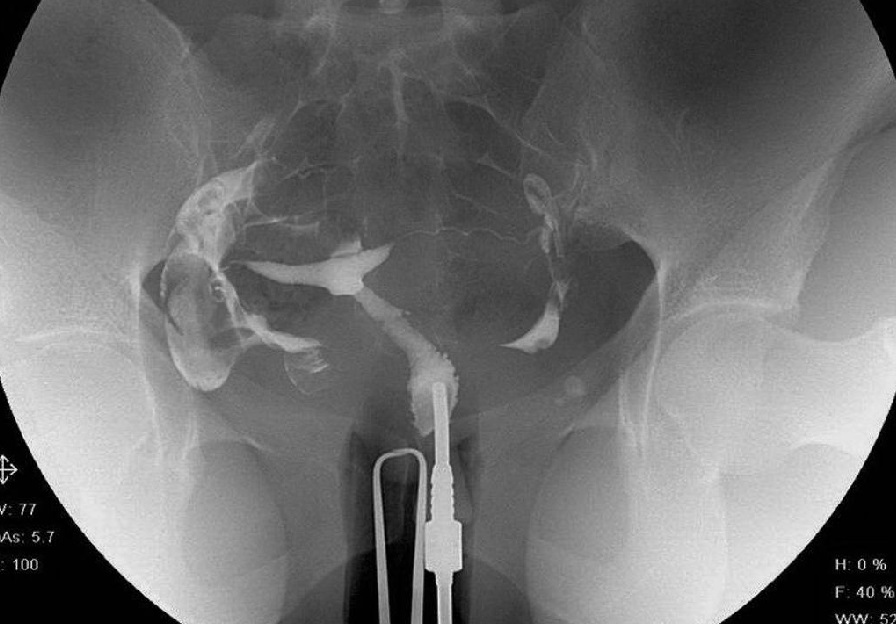

بیمار در وضعیت زنان (به پشت خوابیده، زانوهای خم شده و از هم باز)، زیر دستگاه اشعه ایکس قرار می گیرد. پزشک یک اسپکولوم را وارد واژن میکند، سپس یک کانولا را در دهانه رحم قرار میدهد که از طریق آن یک ماده حاجب تزریق میکند. این به داخل رحم و لوله های فالوپ گسترش می یابد. اشعه ایکس برای مشاهده پیشرفت خوب محصول و تجسم اندام ها گرفته می شود.

هیستروسالپنگوگرافی توسط رادیولوژیست انجام می شود. معاینه بدون بیهوشی انجام می شود. بیمار در موقعیت "زنان و زایمان" مستقر می شود. پزشک اسپکولوم را قرار می دهد، دهانه رحم را ضد عفونی می کند و سپس یک پروب را با روش طبیعی وارد رحم می کند. او به تدریج ماده حاجب را تزریق می کند. به طور معمول، ماده حاجب به تدریج رحم و لوله های فالوپ را کدر می کند تا زمانی که به حفره صفاقی منتقل شود.

چندین عکس رنگی رحم قبل، حین و بعد از تزریق محصول گرفته می شود و این در موقعیت های مختلف:

اشعه ایکس بدون آماده سازی (جستجو برای کلسیفیکاسیون لگن)؛

اشعه ایکس پر شدن ضعیف (پولیپ ها یا فیبروم های زیر مخاطی را برجسته می کند).

اشعه ایکس پر شدن لوله (ارزیابی وضعیت مخاط لوله).

عکس پروفایل (ارزیابی موقعیت رحم و مسیر لوله های فالوپ)؛

اشعه ایکس دیررس (بررسی گردش خون صفاقی، جستجو برای چسبندگی لگن).

در اصل، HSG یک ارزیابی رادیوگرافی از حفره رحم و لوله های فالوپ با استفاده از فلوروسکوپی سرپایی بلادرنگ با تزریق ماده حاجب رادیویی مات از طریق کانال دهانه رحم را نشان می دهد. کانال دهانه رحم، کانتور حفره رحم و لومینای رحم و لوله شامل بخش های قرنیه، ایستمی و آمپولری و تعیین

بیمار باید در وضعیت لیتوتومی پشتی روی میز فلوروسکوپی قرار گیرد و بازوهایش به سمت جانبی یا پشت سر جابجا شده باشند و هیچ تکه فلزی لباس با میدان معاینه تداخل نداشته باشد. سپس یک اسپکولوم در واژن قرار داده می شود و دهانه رحم به روش معمول مشاهده و تمیز می شود.

به طور سنتی، HSG با یک کانول فلزی با نوک بلوط لاستیکی انجام میشود که مهر و موم کافی دهانه رحم را فراهم میکند و اجازه میدهد نوک فلزی بیرون زده در دهانه رحم قرار گیرد، و یک تناکولوم برای تثبیت کانولا در جای خود و امکان تحرک رحم برای اطمینان از حرکت.

روش دیگر، HSG را می توان با یک کاتتر پلاستیکی با یک بالون بادی در نزدیکی نوک آن انجام داد. در روش سوم از یک تناکولوم و یک کاتتر نازک استفاده میشود که گاهی اوقات با یک بلوط کمعمق، بدون بیرون زدگی در کانال دهانه رحم، در مقابل اگزوسرویکس قرار میگیرد. گزارش شده است که این روش کمتر دردناک است و تجسم کامل حفره را فراهم می کند. با تمام تکنیک ها، ماده حاجب باید قبل از قرار دادن از طریق دستگاه تزریق شود تا احتمال تزریق هوا به داخل حفره رحم و ایجاد حباب های هوا کاهش یابد که ممکن است تفسیر را پیچیده کند. .

سپس ابزار مورد نظر در موقعیت قرار می گیرد. اگر از کاتتر بالون استفاده شود، به طور کامل یا حداقل تا حدی که بیمار قادر به تحمل آن است باد میشود. سپس اسپکولوم باید برداشته شود تا کانال دهانه رحم و بخش تحتانی رحم مسدود نشود، مگر اینکه از اسپکولوم پلاستیکی استفاده شود. سپس کشش ملایم قبل و در حین تزریق ماده حاجب اعمال می شود تا در صورت استفاده از تناکولوم، نمای کاملی از رحم به دست آید.

قبل از تزریق ماده حاجب، با قرار دادن وسایل، یک رادیوگرافی پیشاهنگی از لگن گرفته می شود. در مقایسه با گرفتن دهانه رحم پس از بلوک پاراسرویکال برای استفاده از یک کانول فلزی، بادکردن بالون به عنوان ناخوشایندتر توصیف شده است، در حالی که به نظر نمی رسد درد همراه با اتساع کنتراست رحم بین دو روش متفاوت باشد.بی حس کننده های موضعی (مثلاً ژل لیدوکائین) ممکن است درد را در طول عمل کاهش دهد، در حالی که بلوک داخل سرویکس درد را در حین تزریق ماده حاجب به رحم بهبود نمی بخشد.

همچنین میتوان با تزریق آهسته ماده حاجب، درد را به حداقل رساند، که اجازه میدهد تصاویر فلوروسکوپی متناوب از رحم و لولههای فالوپ به دست آید. پر کردن رحم برای ارزیابی هرگونه نقص پر شدن داخل رحمی یا ناهنجاری های کانتور. دوم با رحم کاملا متسع شده برای ارزیابی شکل رحم به دست میآید، اگرچه ممکن است در این مرحله نقصهای کوچک پر شدن پنهان شود.